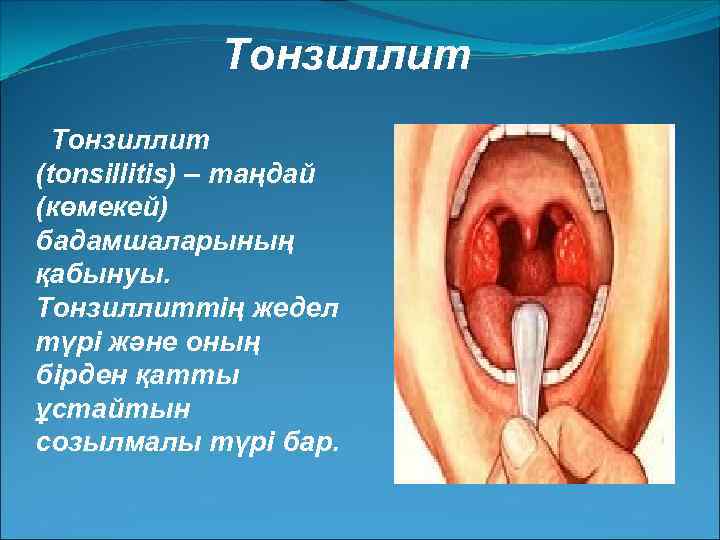

Тонзиллит (tonsіllіtіs) – таңдай (көмекей) бадамшаларының қабынуы. Тонзиллиттің жедел түрі және оның бірден қатты ұстайтын созылмалы түрі бар.

Созылмалы түрі мұрыннан қиналып дем алудан, мұрын қуыстарының және тістің зақымдануынан болады. Бұл кезде қабыну ошағы негізінен бадамша бездің шұңқыры лакунада болады. Науқас адамның оқтын-оқтын тамағы ауырып, жұтынғанда тамағында бір нәрсе тұрғандай сезінеді. Кейде құлақ шаншып ауырады. Ауру адамның дене қызуы 37, 3 – 37, 5 С-қа көтеріліп, дерт бірнеше аптаға, тіпті бірнеше айға созылады.